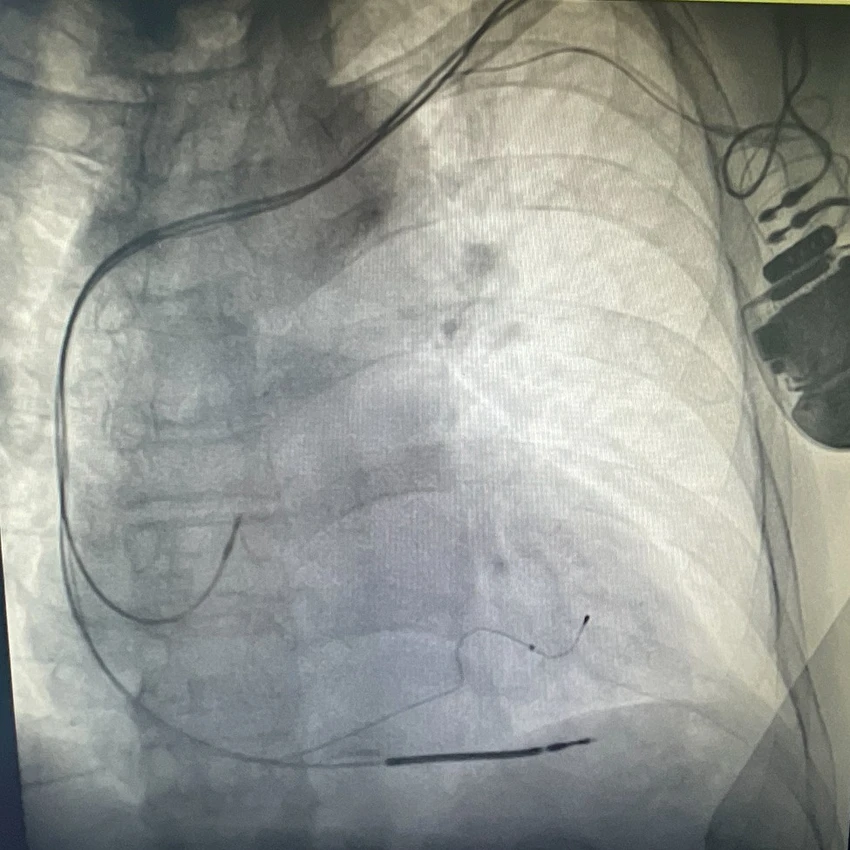

Die Röntgenaufnahme zeigt den implantieren Herzschrittmacher mit Defibrillator.

Da die Batterie nun fast erschöpft war, entschieden sich die behandelnden Ärztinnen und Ärzte für den Einsatz der neuesten Generation der kardialen Resynchronisationstherapie (CRT-Therapie). Valjbona Nelovic, Oberärztin der Klinik für Kardiologie am Klinikum Herford, setzte Burkhard Krake den deutschlandweit ersten „Entrant HF“ CRT-Defibrillator ein. Dieses neue Gerät misst ständig die elektrischen Eigenschaften des Herzens, um seine Aktivität dem Bedarf des Herzens individuell und kontinuierlich anzupassen. Damit kann der Ausgleich einer Herzschwäche besser als mit den sonst üblichen Standardeinstellungen erfolgen. Studien zeigen, dass Patientinnen und Patienten mit aktivierter Technologie 22 Prozent weniger Krankenhausaufenthalte aufgrund von Herzinsuffizienz haben und sich die Synchronität des Herzschlags verbessert.

Burkhard Krake aus Bad Salzuflen lebt seit acht Jahren mit einem Herzschrittmacher mit Defibrillator. Nun erhielt der 78-Jährige in der Klinik für Kardiologie und konservative Intensivmedizin im Klinikum Herford ein neues, hochmodernes Gerät: den „Entrant HF“ CRT-Defibrillator der Firma Abbott, der in der neuesten Generation eine optimierte Therapie für Patientinnen und Patienten mit Herzinsuffizienz bietet.